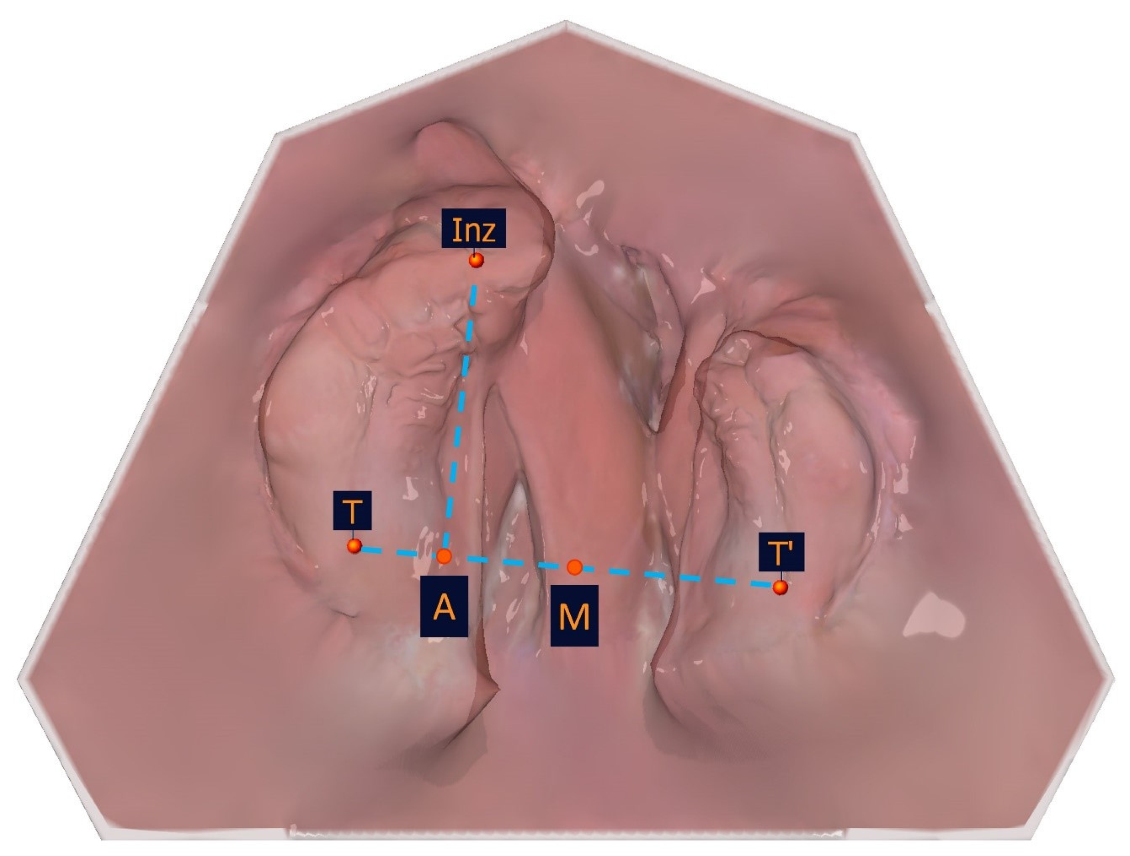

The selection of the measuring points detailed in Table 1 was based on a number of factors, including the publications of Mazaheri et al. [18], Ashley-Montagu [19], Sillman [20], and Robertson [21]. If a point appears on both jaw segments, a ′ indicates that the point is located on the smaller jaw segment. Figure 4 and Table 1 show the measuring points on a dental left-sided cleft lip and palate model.

Figure 4. Illustration of the anatomical measuring points. The anatomical measuring points and their description are presented in Table 1.